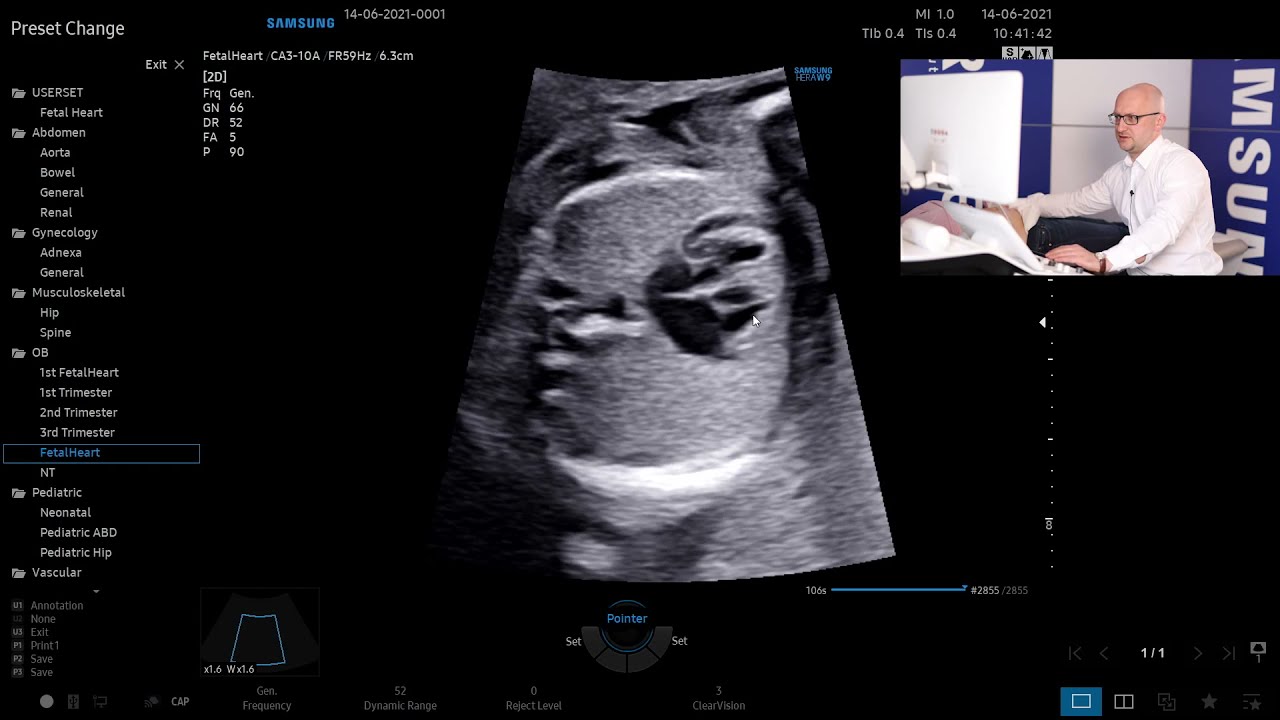

Moje zainteresowania zawodowe obejmują diagnostykę ultrasonograficzną, nieinwazyjną i inwazyjną płodu, terapię płodu, wszelkie problemy ciąży wysokiego ryzyka i zagadnienia w zakresie medycyny matczyno-płodowej, patologii porodu i połogu.

Od 2013 roku biorę udział w pracach Zespołu Ekspertów PTGiP i jestem współautorem ogólnopolskich Rekomendacji w zakresie diagnostyki ultrasonograficznej w ciąży o przebiegu prawidłowym oraz w ginekologii, a także aktualizacji tych Rekomendacji w 2015 roku oraz aktualizacji w 2020 roku. Jestem autorem publikacji, rozdziałów w podręcznikach oraz doniesień zjazdowych z zakresu Położnictwa i Ginekologii , materiałów edukacyjnych dla lekarzy z zakresu ultrasonografii w Perinatologii oraz filmów szkoleniowych na portalach społecznościowych. Jestem trzykrotnym laureatem zespołowej nagrody JM Rektora Uniwersytetu Medycznego w Poznaniu za cykl publikacji i osiągnięcia naukowe.

Od 2008 roku jestem wykładowcą na kursach oraz instruktorem na warsztatach praktycznych "hands-on" z zakresu diagnostyki ultrasonograficznej płodu, pod auspicjami Sekcji USG PTGiP. Brałem udział w kilkudziesięciu kursach krajowych i zagranicznych z zakresu ultrasonografii płodu - jako uczestnik i jako organizator/wykładowca/instruktor.

W 2008 odbyłem miesięczny staż z zakresu ultrasonografii prenatalnej i terapii Fetal Medicine Foundation w Christian Albrechts University, Kilonia, Niemcy - pod kierunkiem prof. Constantina von Kaisenberga. Jestem posiadaczem certyfikatów z zakresu ultrasonografii w Położnictwie i Ginekologii, w tym - certyfikatu Sekcji Ultrasonografii PTGiP w zakresie wykonywania badań prenatalnych, dopplerowskich i echokardiograficznych w Położnictwie, certyfikatu The Fetal Medicine Foundation w zakresie badań prenatalnych w 11–13+6 tygodniu ciąży - przezierność karku u płodu (NT), kość nosowa u płodu (NB), przepływ w przewodzie żylnym u płodu (DV), przepływ na zastawce trójdzielnej (TR) oraz przepływ tętnicy macicznej oraz w zakresie badań dopplerowskich w ciąży.